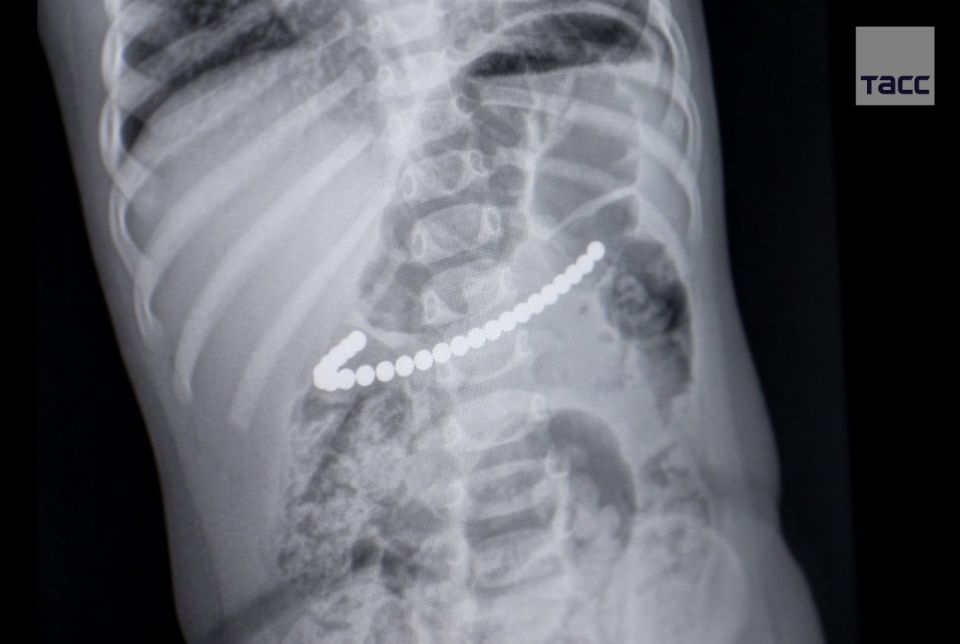

Малышку с шариками в желудке (24 штуки) доставили в детскую областную больницу. Вмешательство провели в тот же день. Магниты были соединены друг с другом настолько сильно, что извлечь их удалось единой цепочкой.Написать Telegram...

Шарики были крепко соединены друг с другом в желудке ребенка в единую цепочку, которая одним концом уходила в область 12-перстной кишки. Медики извлекли их эндоскопическим путем.Сейчас девочка получает консервативное лечение в хирургическом отделении...